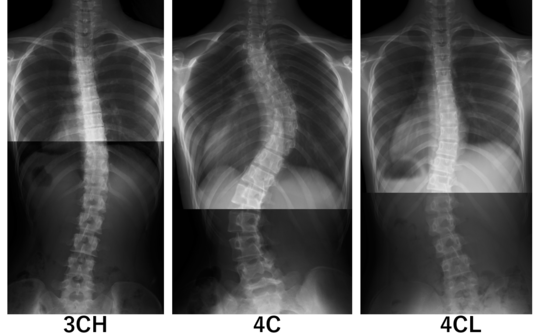

シュロス分類(シュロスセラピーより)

側弯症のカーブパターンは無数にある訳ではなく、ある一定のパターンに分けられます。シュロス法では側弯のカーブパターンを7パターンに分類します。

この分類は患者様の外観の状態とレントゲン画像を合わせて評価・判断します。​

カーブパターンの一部

この写真は胸椎右凸(胸椎が右にカーブしている)のいくつかのパターンです。実際は左右が反転した胸椎左凸のパターンもあるため7パターン×2のバリエーションがあると言えます。